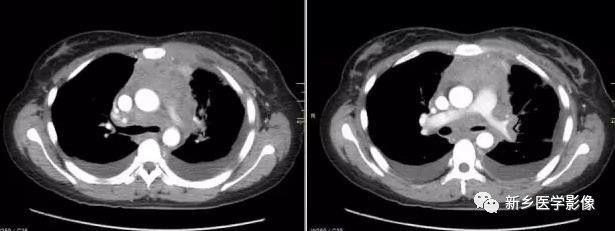

2.CT表现:前纵隔、中纵隔多组淋巴结肿大,常融合成块,尤其易累及血管前间隙组、主动脉弓旁、上腔静脉后组为最多见,易包绕上腔静脉等大血管及气管。肿块多呈均匀软组织密度,分叶状。轻到中度强化。放疗后肿块内易出现坏死、囊变、钙化灶。病人多伴有全身其他部位的淋巴结肿大。

3.MRI表现:肿大的淋巴结信号通常均匀,T1WI呈等或稍低信号,T2WI呈稍高信号。放疗后的纤维化在T2WI呈低信号,残余活动性肿瘤则为较高信号。